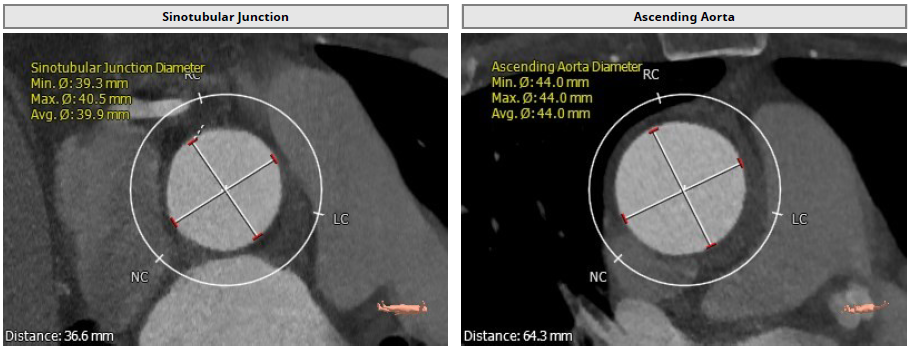

1.患者主动脉瓣三叶式,瓣叶基本等大,瓣叶增厚,瓣叶未见明显钙化;

2.患者主动脉瓣环周长折算直径约30.1mm;

3.患者双侧冠脉开口高度可LCA:16.2mm,RCA:21.8mm;

4.患者术中造影角度LAO:7°,CAU:1°。

Annulus: 30.1mm

环上结构折算直径:30.3mm ;主动脉瓣环夹角:135°

左冠高度:16.2mm;右冠高度:21.8mm

LVOT: 31.5mm;窦部直径:42.7/42.0/46.9mm

窦管交界:39.9mm;升主动脉:44mm

术中造影角度LAO: 7°,Caudal: 1°